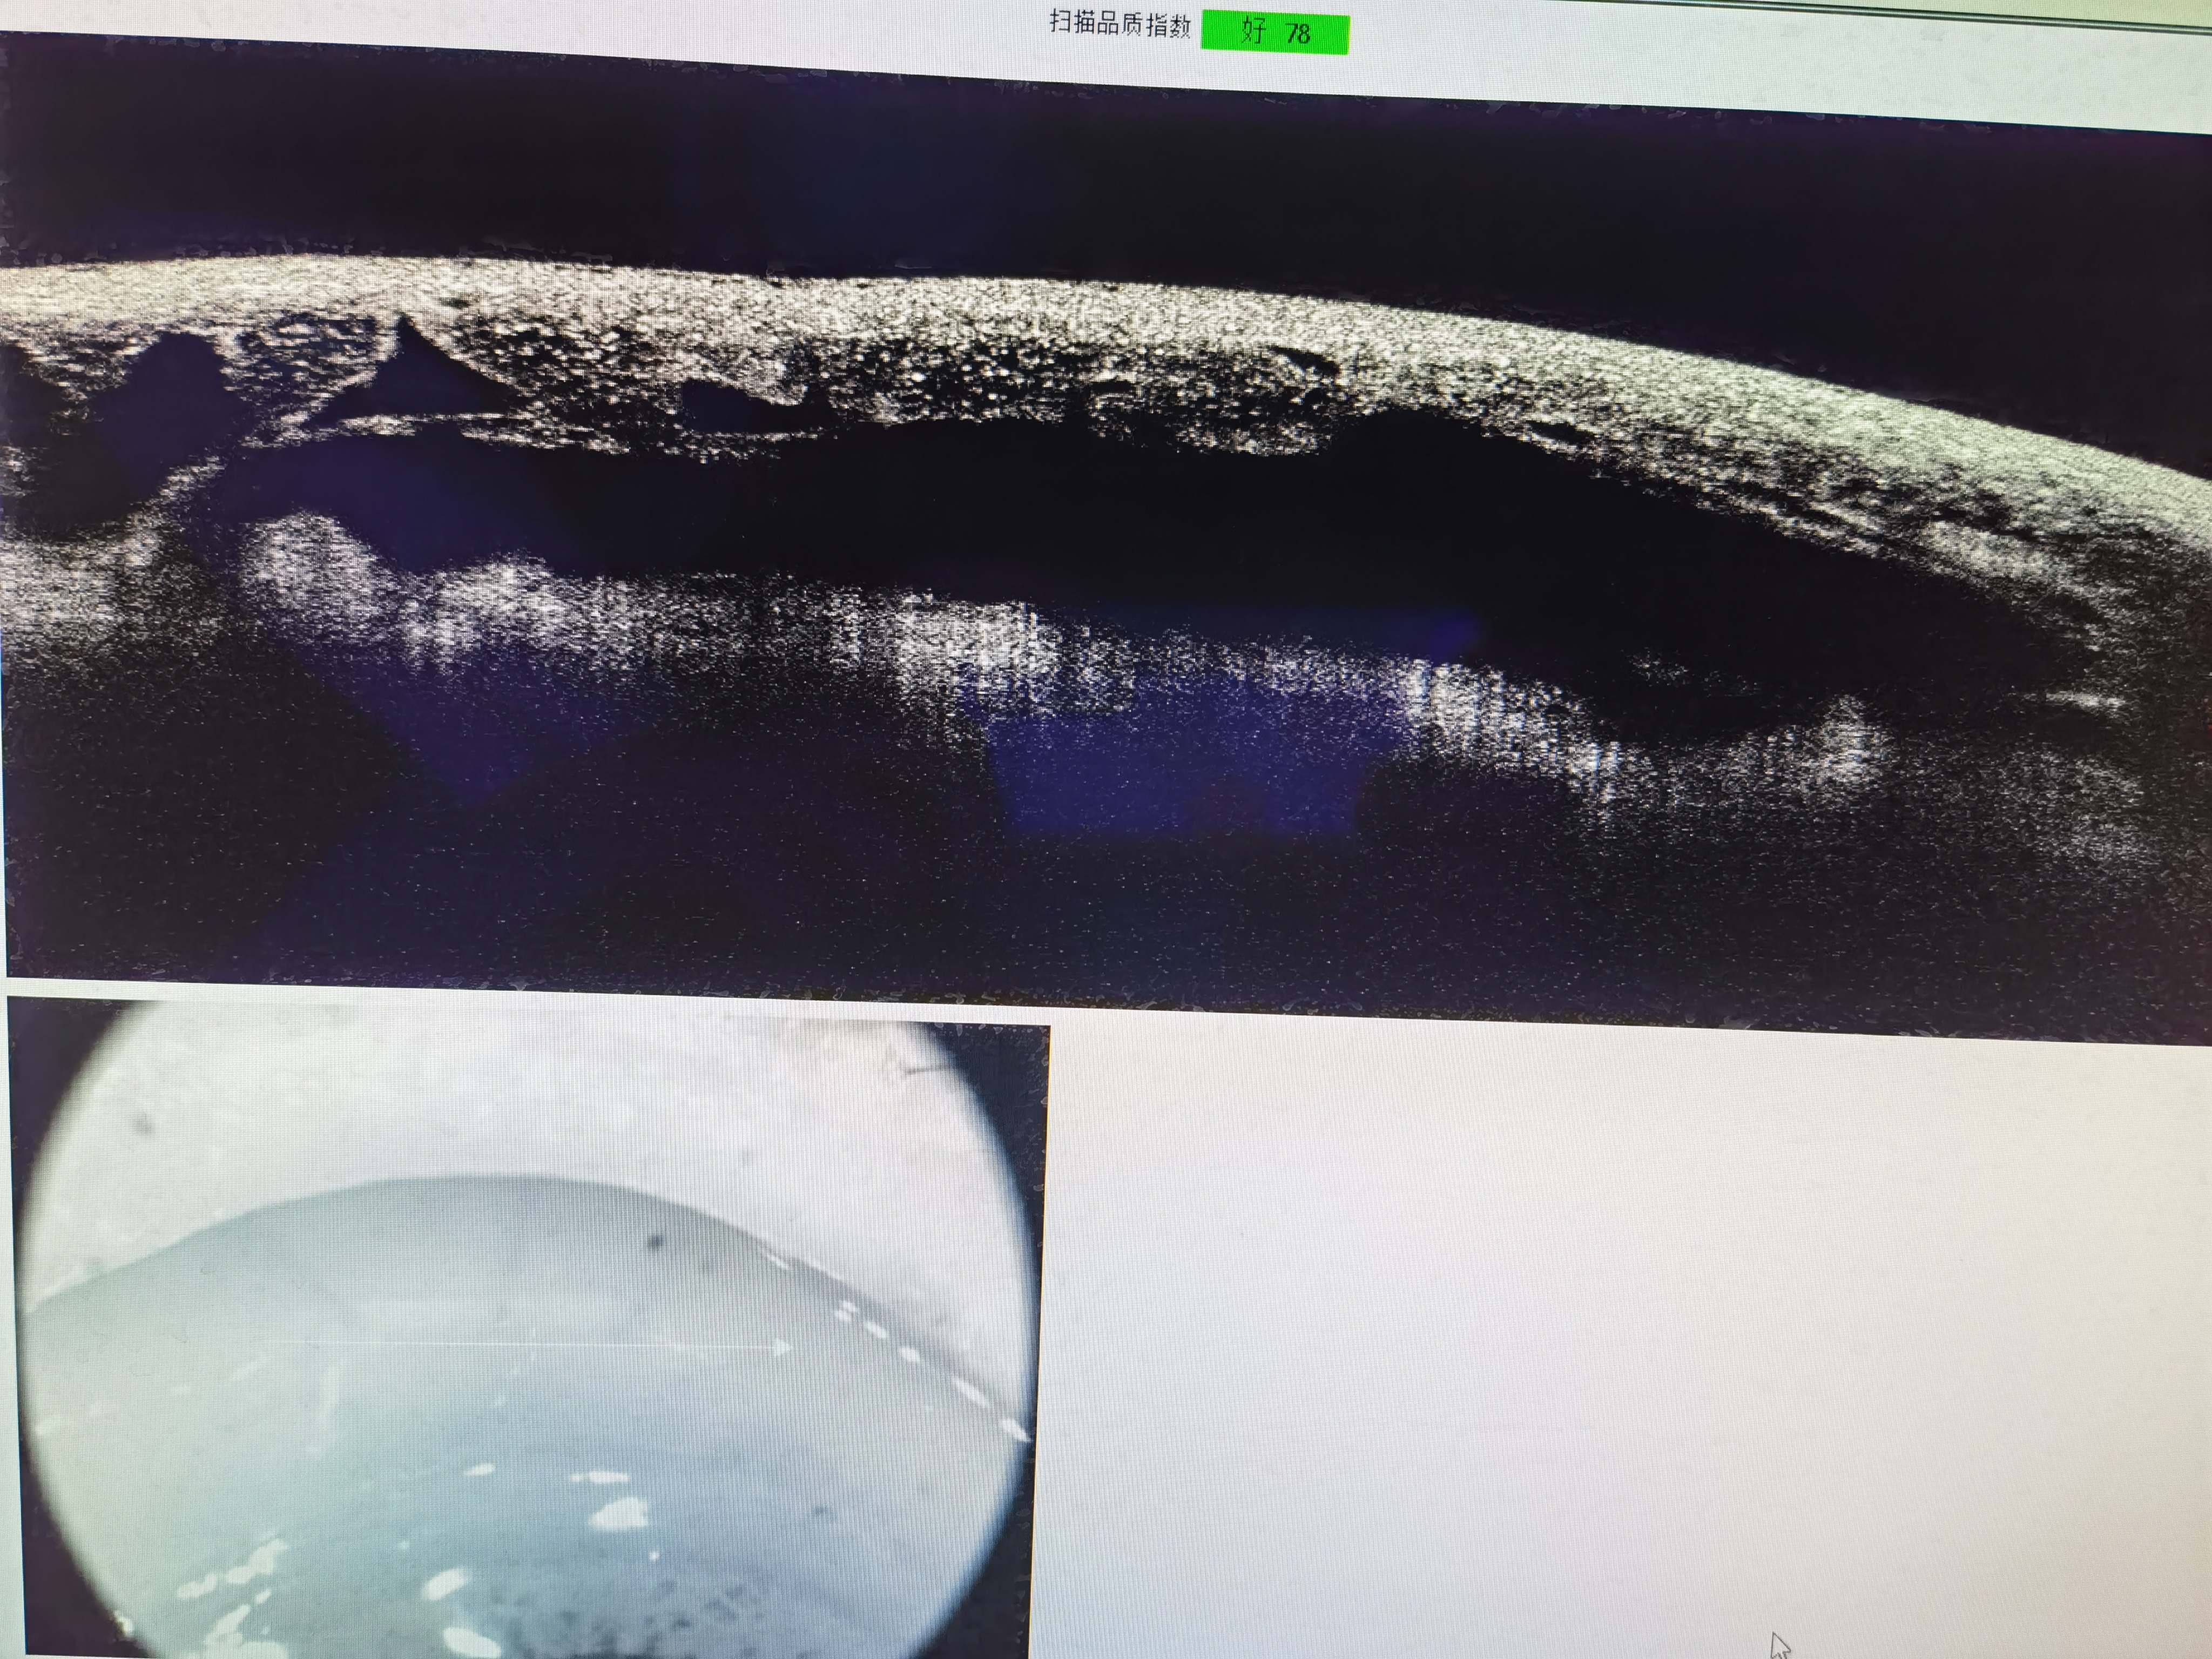

术后第一天前房深度正常

术后巩膜池形成良好